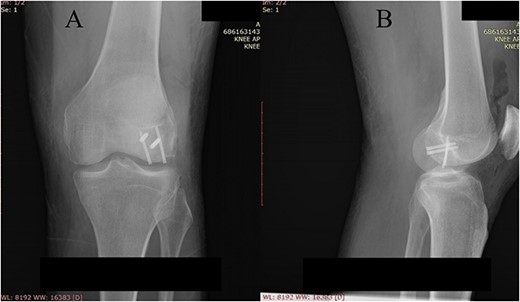

A plain X-ray of the left knee revealed a single defect of the lateral femoral condyle in the anteroposterior (AP) view. The lateral view showed a free bone fragment with a defect (Fig. 1A and B). Additional diagnostic imaging was performed. A computerized tomography (CT) scan revealed multifragmentary (three fragments) fracture of the lateral femoral condyle accompanied by a fracture of the left patella (Fig. 2). The fracture was classified as 33B3.2 according to the Association for Osteosynthesis–Orthopaedic Trauma Association (AO/OTA), Type II C (according to Letenneur) [2]. It was decided that single-approach surgery (posterior or anterior) would be insufficient for acceptable anatomic reduction and proper fixation of all the fragments because of the fracture complexity. The preoperative plan consisted of a posterior-first approach (extended posterior approach to the proximal tibia) for fixation of the largest (posterior) fragment (Fig. 3) followed by an arthroscopic anterior approach (for anterior fragment fixation). The predetermined time interval between the two procedures was to allow the healing of the joint capsule after the index surgery. Operative fixation of the patellar fracture was not indicated.

Plain X-ray of the left knee. (A) Anteroposterior view of the left knee with visible bone defect in the lateral femoral condyle (arrow). (B) Lateral view of the left knee with visible free bone fragment (arrow).